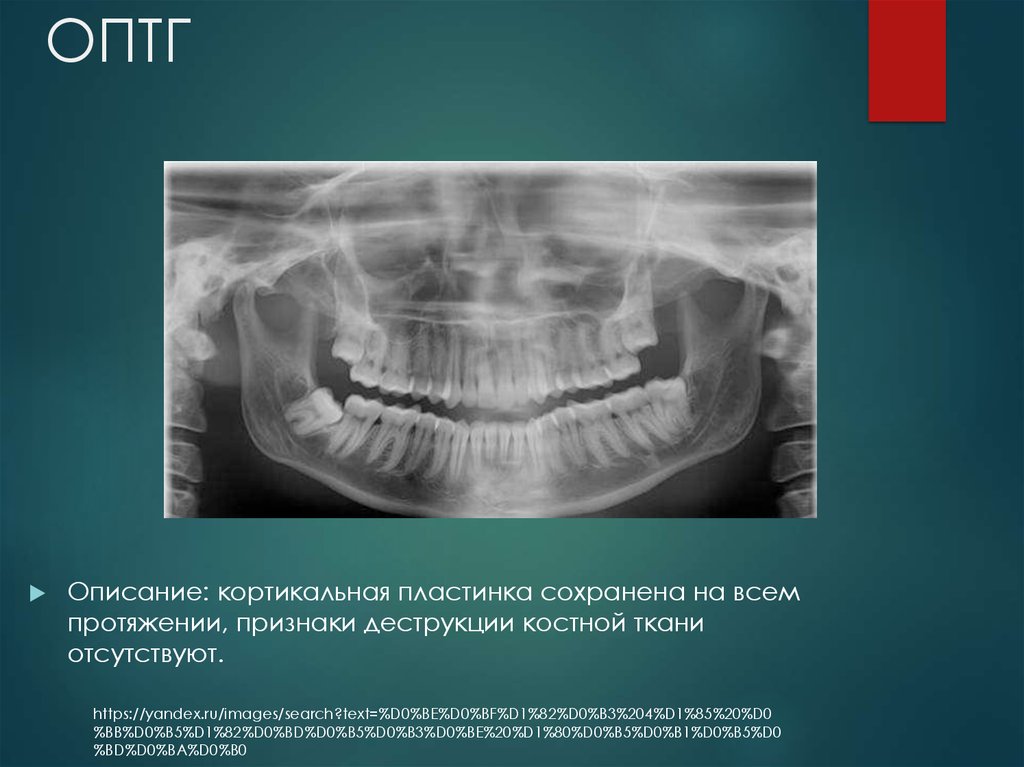

Медицинские Исследования: Кортикальная Пластинка на ОПТГ